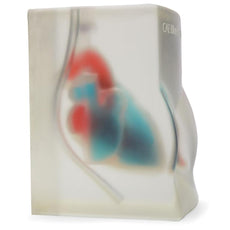

The model is of a supine adult male and extends from the upper buttocks to the lower neck. Positioned in the mid scapulary line, the ultrasound tissue insert contains chest wall superficial tissue, 6th, 7th, 8th, and 9th ribs and intercostal spaces, pleural cavity with lung and atelectatic lung, diaphragm, and superior spleen. The pleural fluid collections allow users to develop and refine their ultrasound guided thoracentesis skills. This model is extremely realistic and is self-healing offering you superb training with a low cost of ownership.

Blue Phantom's mid-scapular thoracentesis ultrasound training model is specifically designed for ultrasound guided thoracentesis procedures. This ultrasound training phantom aids users in developing and practicing the skills associated with a mid scapulary approach to ultrasound guided thoracentesis procedures. This model is excellent for assisting clinicians in gaining proficiency in using ultrasound to identify and guide needle and small gauge catheter insertions in a patient with pleural effusions for diagnostic and/or therapeutic purposes.The model is of a supine adult male and extends from the upper buttocks to the lower neck. Positioned in the mid scapulary line, the ultrasound tissue insert contains chest wall superficial tissue, 6th, 7th, 8th, and 9th ribs and intercostal spaces, pleural cavity with lung and atelectatic lung, diaphragm, and superior spleen. The pleural fluid collections allow users to develop and refine their ultrasound guided thoracentesis skills. This model is extremely realistic and is self-healing offering you superb training with a low cost of ownership.

- Ultrasound tissue module contains the chest wall superficial tissue, 6th, 7th, 8th, and 9th ribs and intercostal spaces, pleural cavity with lung and atelectatic lung, diaphragm, and superior spleen.

ANATOMY:

Chest wall

Pleural cavity

Lung

Atelectatic lung

Ribs

Variety of pleural effusion fluid pockets

Skin layers

Fat

Ribs

Pleural lining